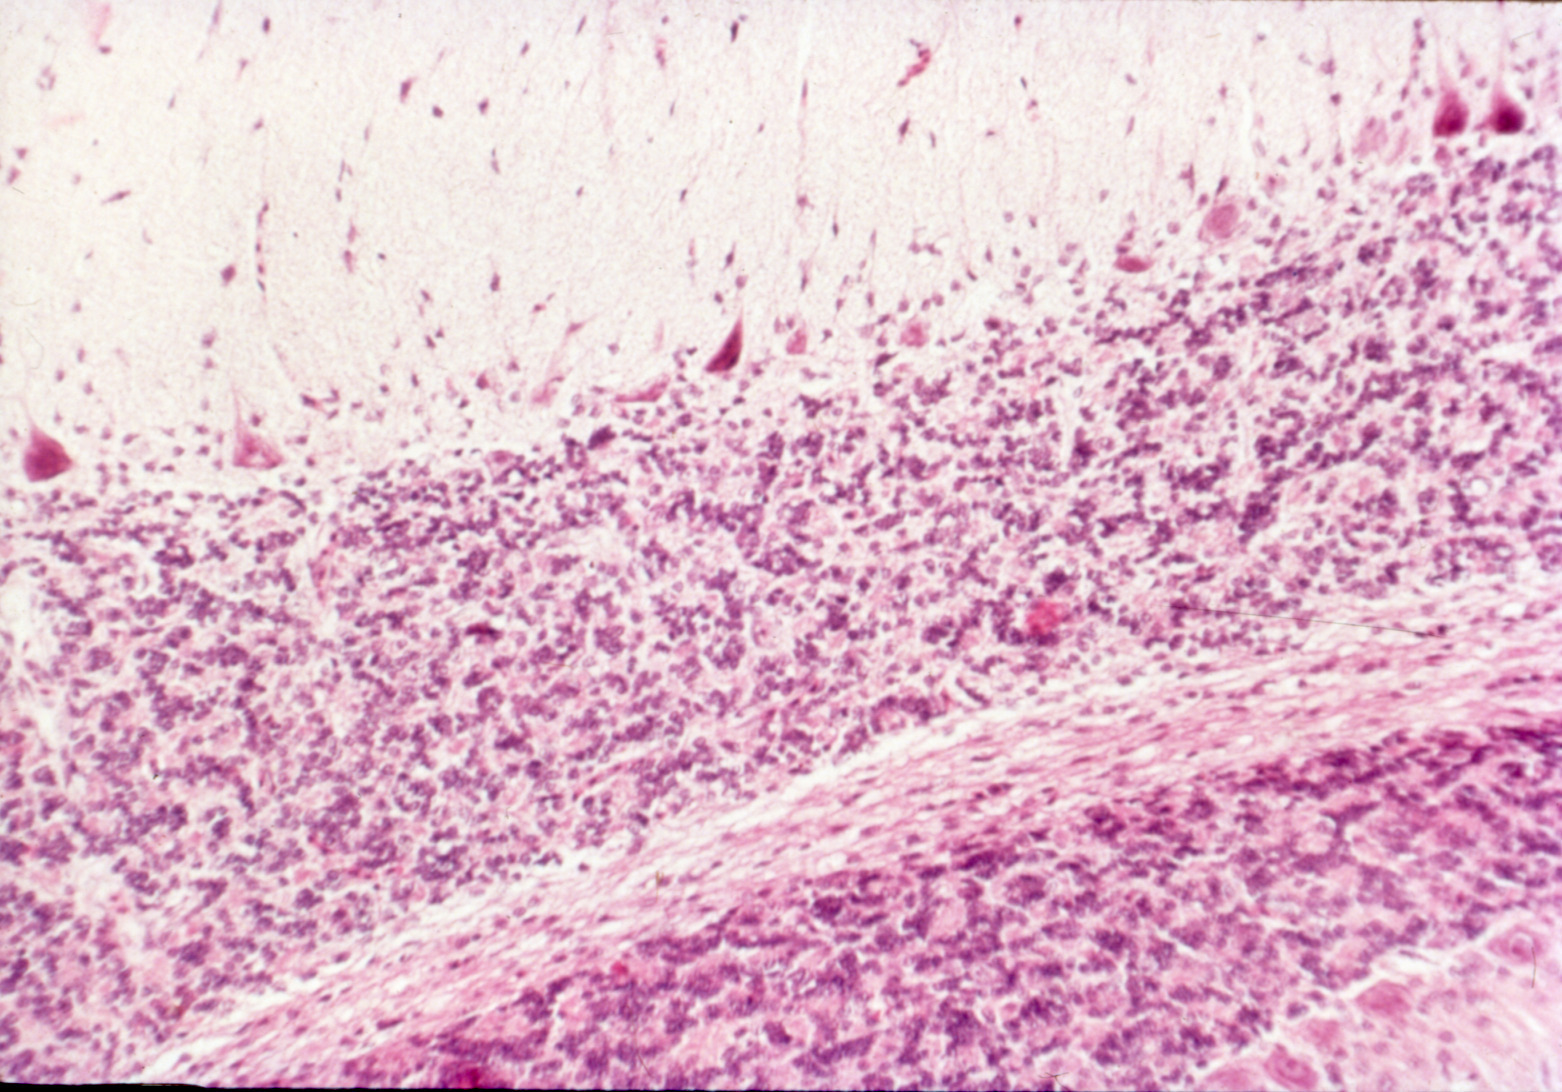

Avian encephalomyelitis (slide study set no. 5)

Avian encephalomyelitis Avian medicine Chickens--Diseases Turkeys--Diseases Pheasants--Diseases

Slide Study Set #5, Avian Encephalomyelitis, 2 sets (includes 32 color slides), 1974